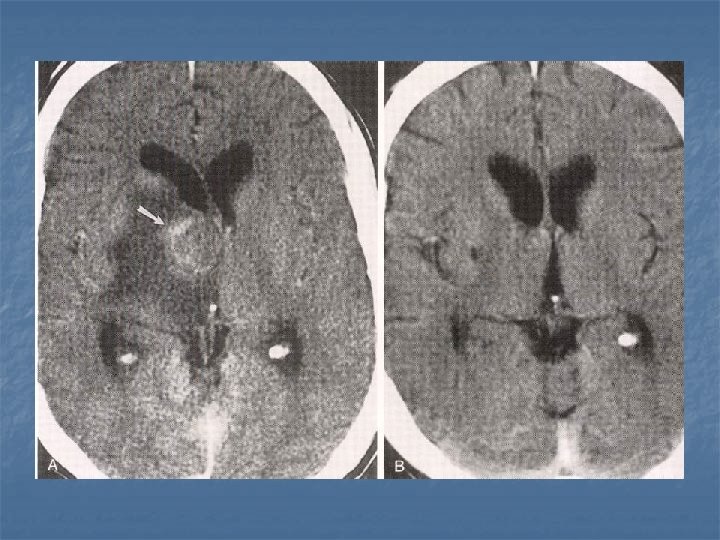

Toxoplasmosis n n n Yer kaplayan lezyonların % 60’ı % 30 olguda mevcut Kortikomedüller bileşke (? ), basal ganglion ve talamusda sık tutulum BT-MR. . . >5 lezyon, halka tarzında kontrast (+), nodüler, ödem ve kitle etkisi Erken tanı önemli. . . tedavi edilebilir 2 hafta primethamine+sulfadiazine